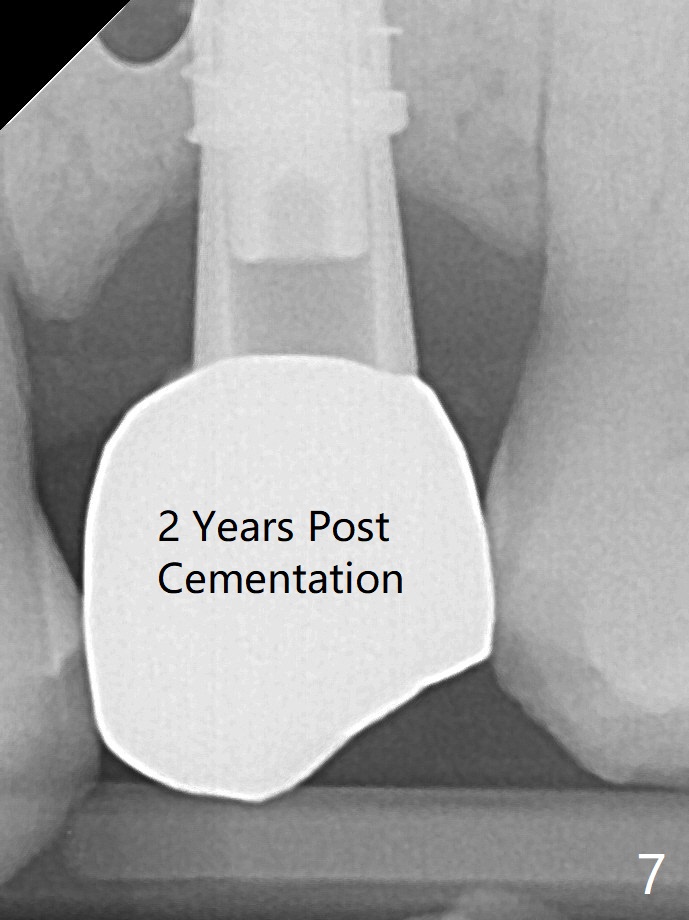

A 4x13 mm IBS implant is seated incompletely.  The osteotomy is further enlarged by 3.8 mm Magic Drill for 11 mm and deepened with 3 mm drill until 18 mm.  Finally the implant is placed at a satisfactory level with insertion torque > 50 Ncm (Fig.5).  The patient chooses to return for impression 6 months postop (Fig.6).  The abutment changes to a 4x4(4) mm one.  The crown is recemented  nearly 2 years post cementation, which is related to distal and deep placement of the implant and bruxism (Fig.7).